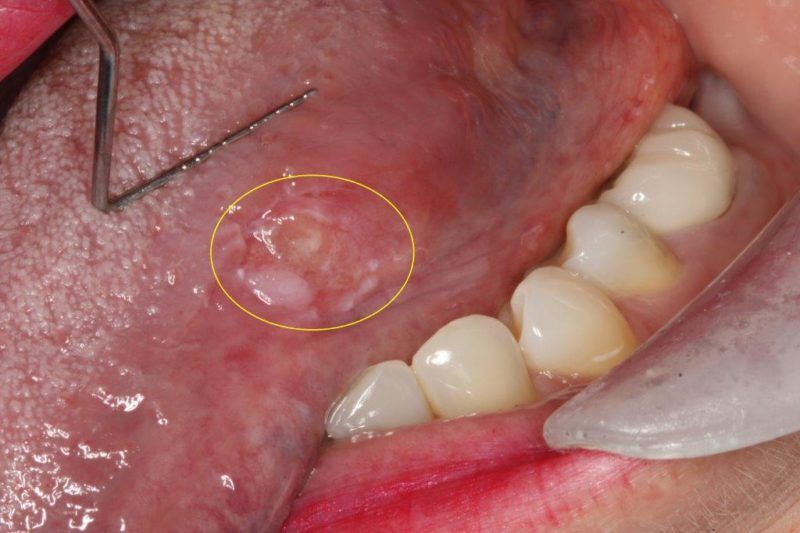

Oral Cancer Screening

Every time you come into Deluxe Dentistry for examination, our hygienist and dentist will screen you for oral, head, and neck cancer. You will feel comfortable and safe knowing two professionals took the time to screen you carefully for a disease that would lead to serious problems if undiagnosed, diagnosed late, or left untreated.